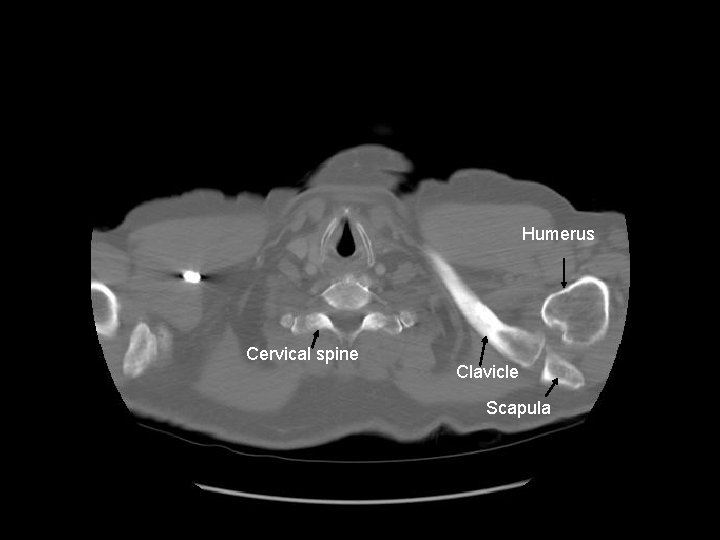

Humerus Cervical spine Clavicle Scapula